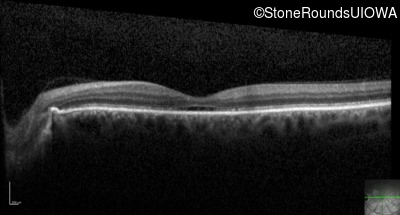

Optical Coherence Tomography - Right - 20/160 -1

Exemplar / OCT Stack

Optical Coherence Tomography - Left - 20/160